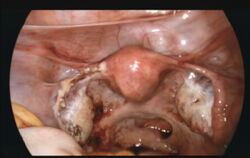

![]() | |

| Laparoscopic view, looking down at the uterus (marked by blue arrows). In the left fallopian tube, there is an ectopic pregnancy and bleeding (marked by red arrows). The right tube is normal. | |